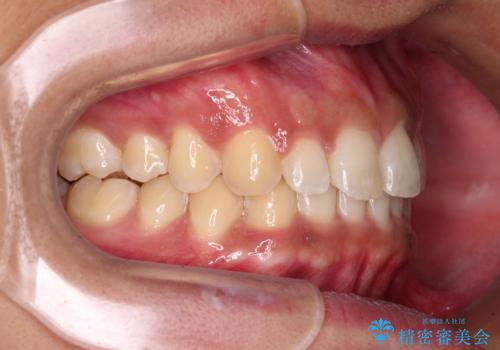

デコボコとディープバイトを治したい インビザラインによる矯正治療

- 前歯のデコボコや隙間と深い咬み合わせ(ディープバイト)を気にして来院された患者様です。

インビザラインによる上下歯列の側方拡大と後方移動、IPR(歯と歯の間を削る)にるスペースの獲得により、デコボコとディープバイトを改善することとしました。

気になっていたデコボコや隙間は改善し、きれいな歯列に整えることができました。

咬合力が非常に強い方であったため、これ以上のディープバイトの改善は困難となりました。